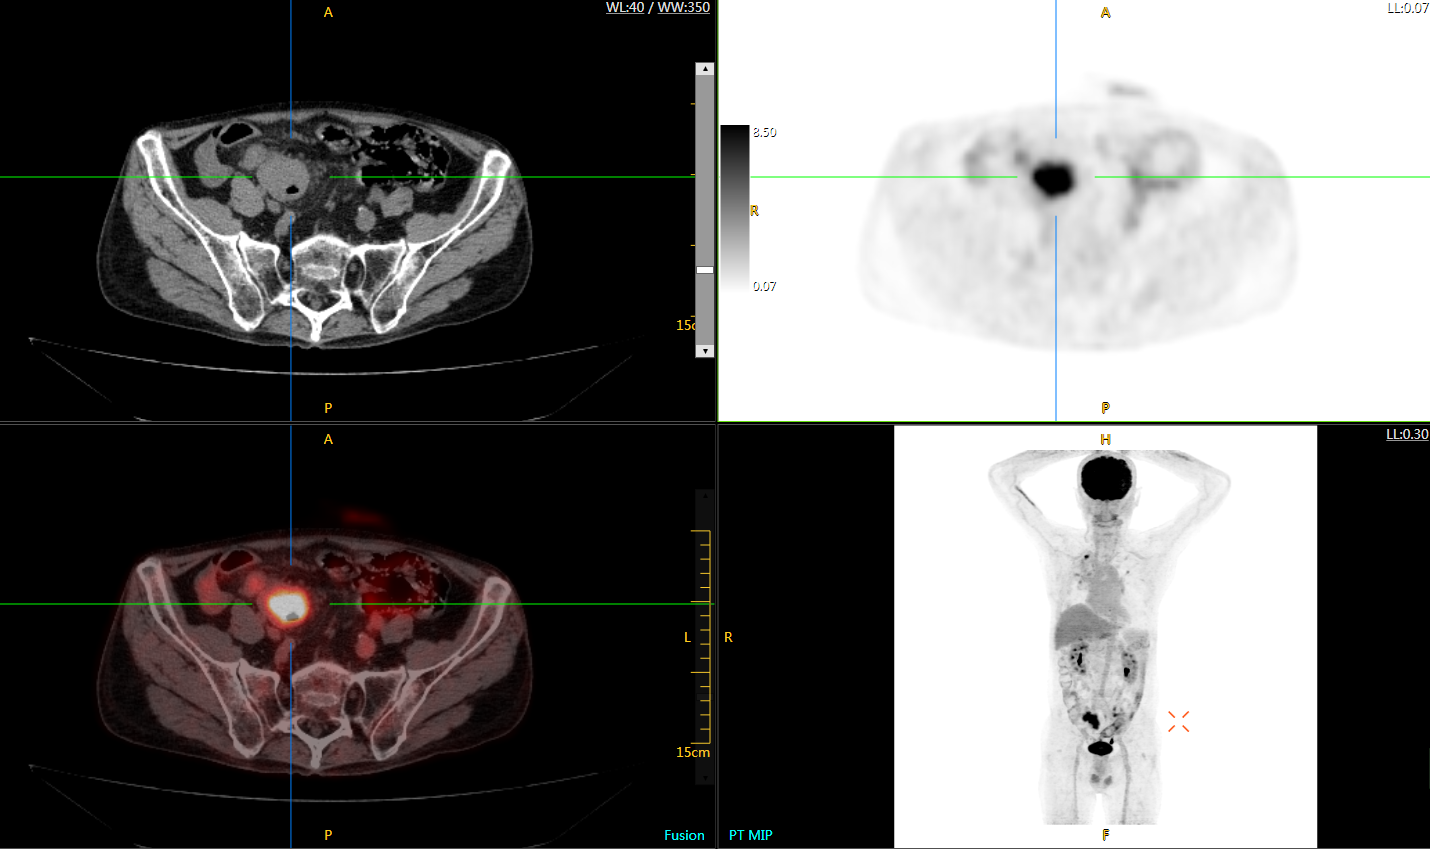

uExplorer探索者不再局限于傳統(tǒng)靜態(tài)代謝過程3D成像,而是在此基礎(chǔ)上新增一個(gè)維度——時(shí)間,從而實(shí)現(xiàn)4D全景成像。

注射總劑量為7.8mCi,14分鐘全身采集時(shí)間,在擁有超高靈敏度與超高分辨率的uEXPLORER上,即可得到展示顯示人體諸多精細(xì)結(jié)構(gòu)的高清三維圖像。

注射總劑量為7.8mCi,注射后1.6小時(shí),基于uEXPLORER探索者掃描1分鐘的圖像

注射總劑量為0.67 mCi FDG(低于常規(guī)劑量的十分之一),基于uEXPLORER探索者掃描15分鐘的圖像

注射總劑量為6.9mCi,注射后10小時(shí),基于uEXPLORER探索者掃描14分鐘的圖像